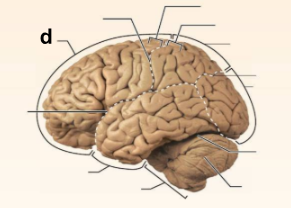

Identify the structure labeled “a” in the image.

Brain Stem

Identify the structure labeled “b” in the image.

Central culcus

Identify the structure labeled “c” in the image.

Cerebellum

Identify the structure labeled “d” in the image.

Frontal lobe

Identify the structure labeled “e” in the image.

Lateral sulcus

Identify the structure labeled “f” in the image.

Occipital lobe

Identify the structure labeled “g” in the image.

Parietal lobe

Identify the structure labeled “h” in the image.

Parieto-occipital sulcus

Identify the structure labeled “i” in the image.

Postcentral gyrus

Identify the structure labeled “j” in the image.

Precentral gyrus

Identify the structure labeled “k” in the image.

Temporal lobe

Identify the structure labeled “l” in the image.

Transverse cerebral fissure